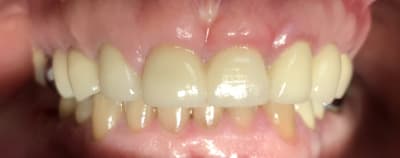

Sethef

12/09/2020 à 12h42

Justement, si ce n'était que bruxisme (chimico induit), l'usure serait généralisée. Un buvard entre les dents de devant?

Le nouveau nous a dit qu’ils étaient plusieurs à avoir ça dans sa famille. Ils sont quand même pas tous camés dans la famille.

Ca parait pas bien possible. Le type n'a que 24 ans!

quelle est la demande du patient avant tout

et subsidiairement combien de dentistes a t il deja consulté

En attendant que le nouveau réponde ... Dans un style différent : 38 ans . très complexé. Aucun dentiste n’a voulu le toucher (pour le secteur antérieur) . Je lui ai dit qu’il fallait lui déglinguer la mâchoire. Sauf qu’il ne veut pas faire de chirurgie orthognatique, c’est sa seule condition . Par contre est prêt à mettre n’importe quel prix pour retrouver un beau sourire. N’est ni fermé à l’ortho , ni fermé à l’implantologie.

Photo de la pano qu’il m’a ramenée.

On se passera des : faut faire un détartrage :) , ou faut qu’il se lave les dents.

Ex des centrales et bridge 12-22, je pense que tu peux faire un truc sympa. Teste sur ton plâtre.

Mouais, mouais, mouais... Très complexé... Le problème, c'est que ça se limite pas qu'au dent...

Pour moi, ortho, orthopédie ou rien. J'aime bien rien.

c'est clair que tu peux faire un truc sympa

à condition de maitriser l'hygiene avant tout et de preserver les canines à tout prix

et à condition que l'occlusion soit bien tolérée examen soigneux des ATM et des muscles masticateurs

la seule solution esthétique pour ne pas lui faire des contrales de lapin passe par une fausse gencive

40 ans d'expérience me disent qu'aucune soltion fixe ne serait durable

38 ans ?? Je lui en donne 55...

Le cas du début c'est avant tout une supraclusie carabinée.

Faut voir si il serre les dents, comment il respire et deglutit....

Gouttières dures chiadées oclusalement, le lieux étant qu'il puisse bouffer avec.

Comme ça tu peux remonter en postérieur et te donner une chance de réhabiliter devant.

Si et seulement si il supporte alors restaurations résine en postérieur et devant ensuite.